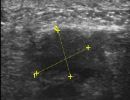

Foot Tendons

Foot Ultrasound allows the diagnosis of tendonitis, tenosynovitis, and rupture in the following tendons:

- Achilles Tendon

- Peroneal Tendons

- Flexor Tendons

- Extensor Tendons